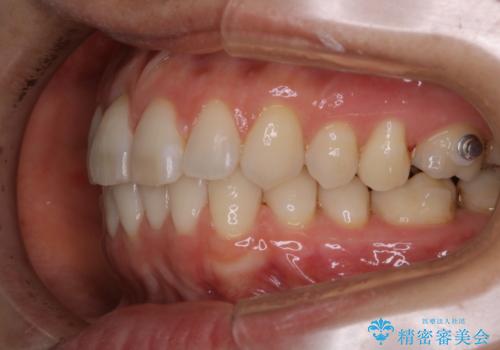

- インビザライン矯正治療中にステインが気になるとのことで来院されました。全体的にステインが付着していたため自費クリーニングPMTC(60分コース)を行いました。

インビザライン矯正治療中は、ご自身の歯にアタッチメントという突起物(効率的に歯の移動を行うため)をつけます。そのため、通常時よりもステインが付きやすい状態になることがあります。

インビザラインは透明なマウスピースなので、ご自身の歯にステインなどが付着していると、見た目に影響してしまうことがあります。